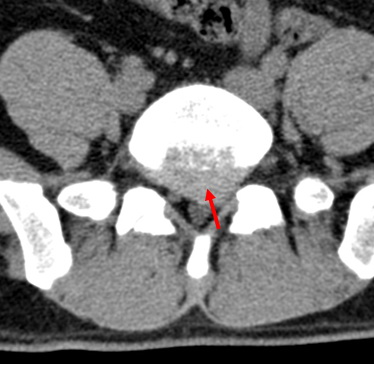

患者腰椎CT显示L5-S1椎间盘突出明显,压迫左侧神经根。